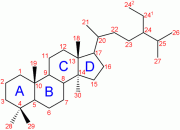

| 06:49, 28 בפברואר 2024 | Ketosteroid 1.png (קובץ) |  |

7 קילו־בייטים | Motyk | 1 | |